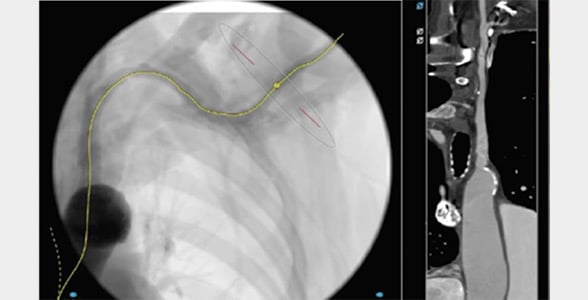

- Prefer left axillary in most cases for a more favorable orientation to the aortic valve; reserve the right axillary artery for cases where the left is unsuitable (Figures 1- 5).

Figure 5: Center line and straight view

- Use fluoroscopy landmarks to remain safely along the rib-cage side and avoid pleural entry.

- Perform angiography with backup wire inside the vessel to evaluate its arrangement and decide the puncture axis (essential for traversing the vessel with the introducer and delivery)